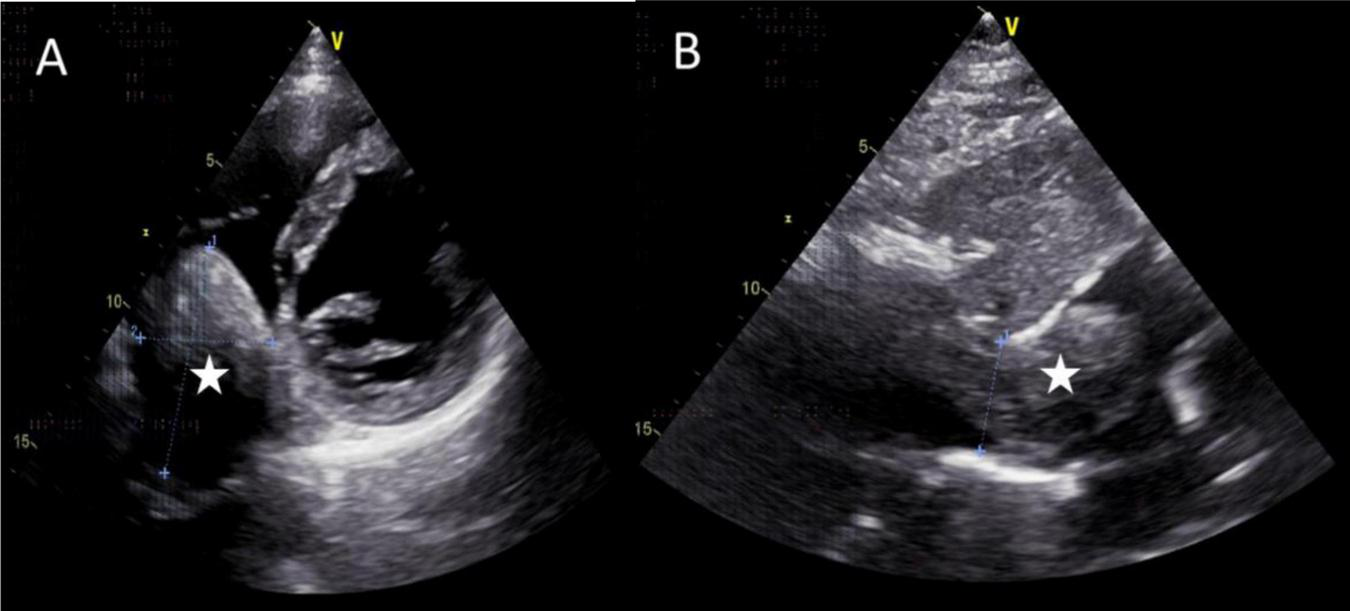

The mass can also be visualized within the right atrium and inferior vena cava using gray scale ultrasound imaging, appearing as a hypoechoic lesion of considerable length (Figure 3). Additionally, color Doppler ultrasonography can be utilized to assess hepatic vein obstruction and the direction of hepatic blood reflux. We can see that there is obstruction in the blood flow of the left and middle hepatic veins, resulting in a reversal of blood flow from the left hepatic vein into the middle hepatic vein (Figure 4). This obstruction has led to the formation of multiple collateral circulations between the middle hepatic vein and either the right hepatic vein or the dilated accessory hepatic vein in the posterior right lobe (Figure 5). These collateral circulations serve to drain the blood flow from the distal segment of the middle hepatic vein and the left hepatic vein into the inferior vena cava.

FIGURE 3

Images of transthoracic echocardiogram. (A,B) The asterisks indicated the hypoechoic mass located within the right atrium and inferior vena cava, measuring 6.3 cm × 4.8 cm in dimensions. (B) The inferior vena cava exhibited dilation with a proximal diameter of 3.1 cm.